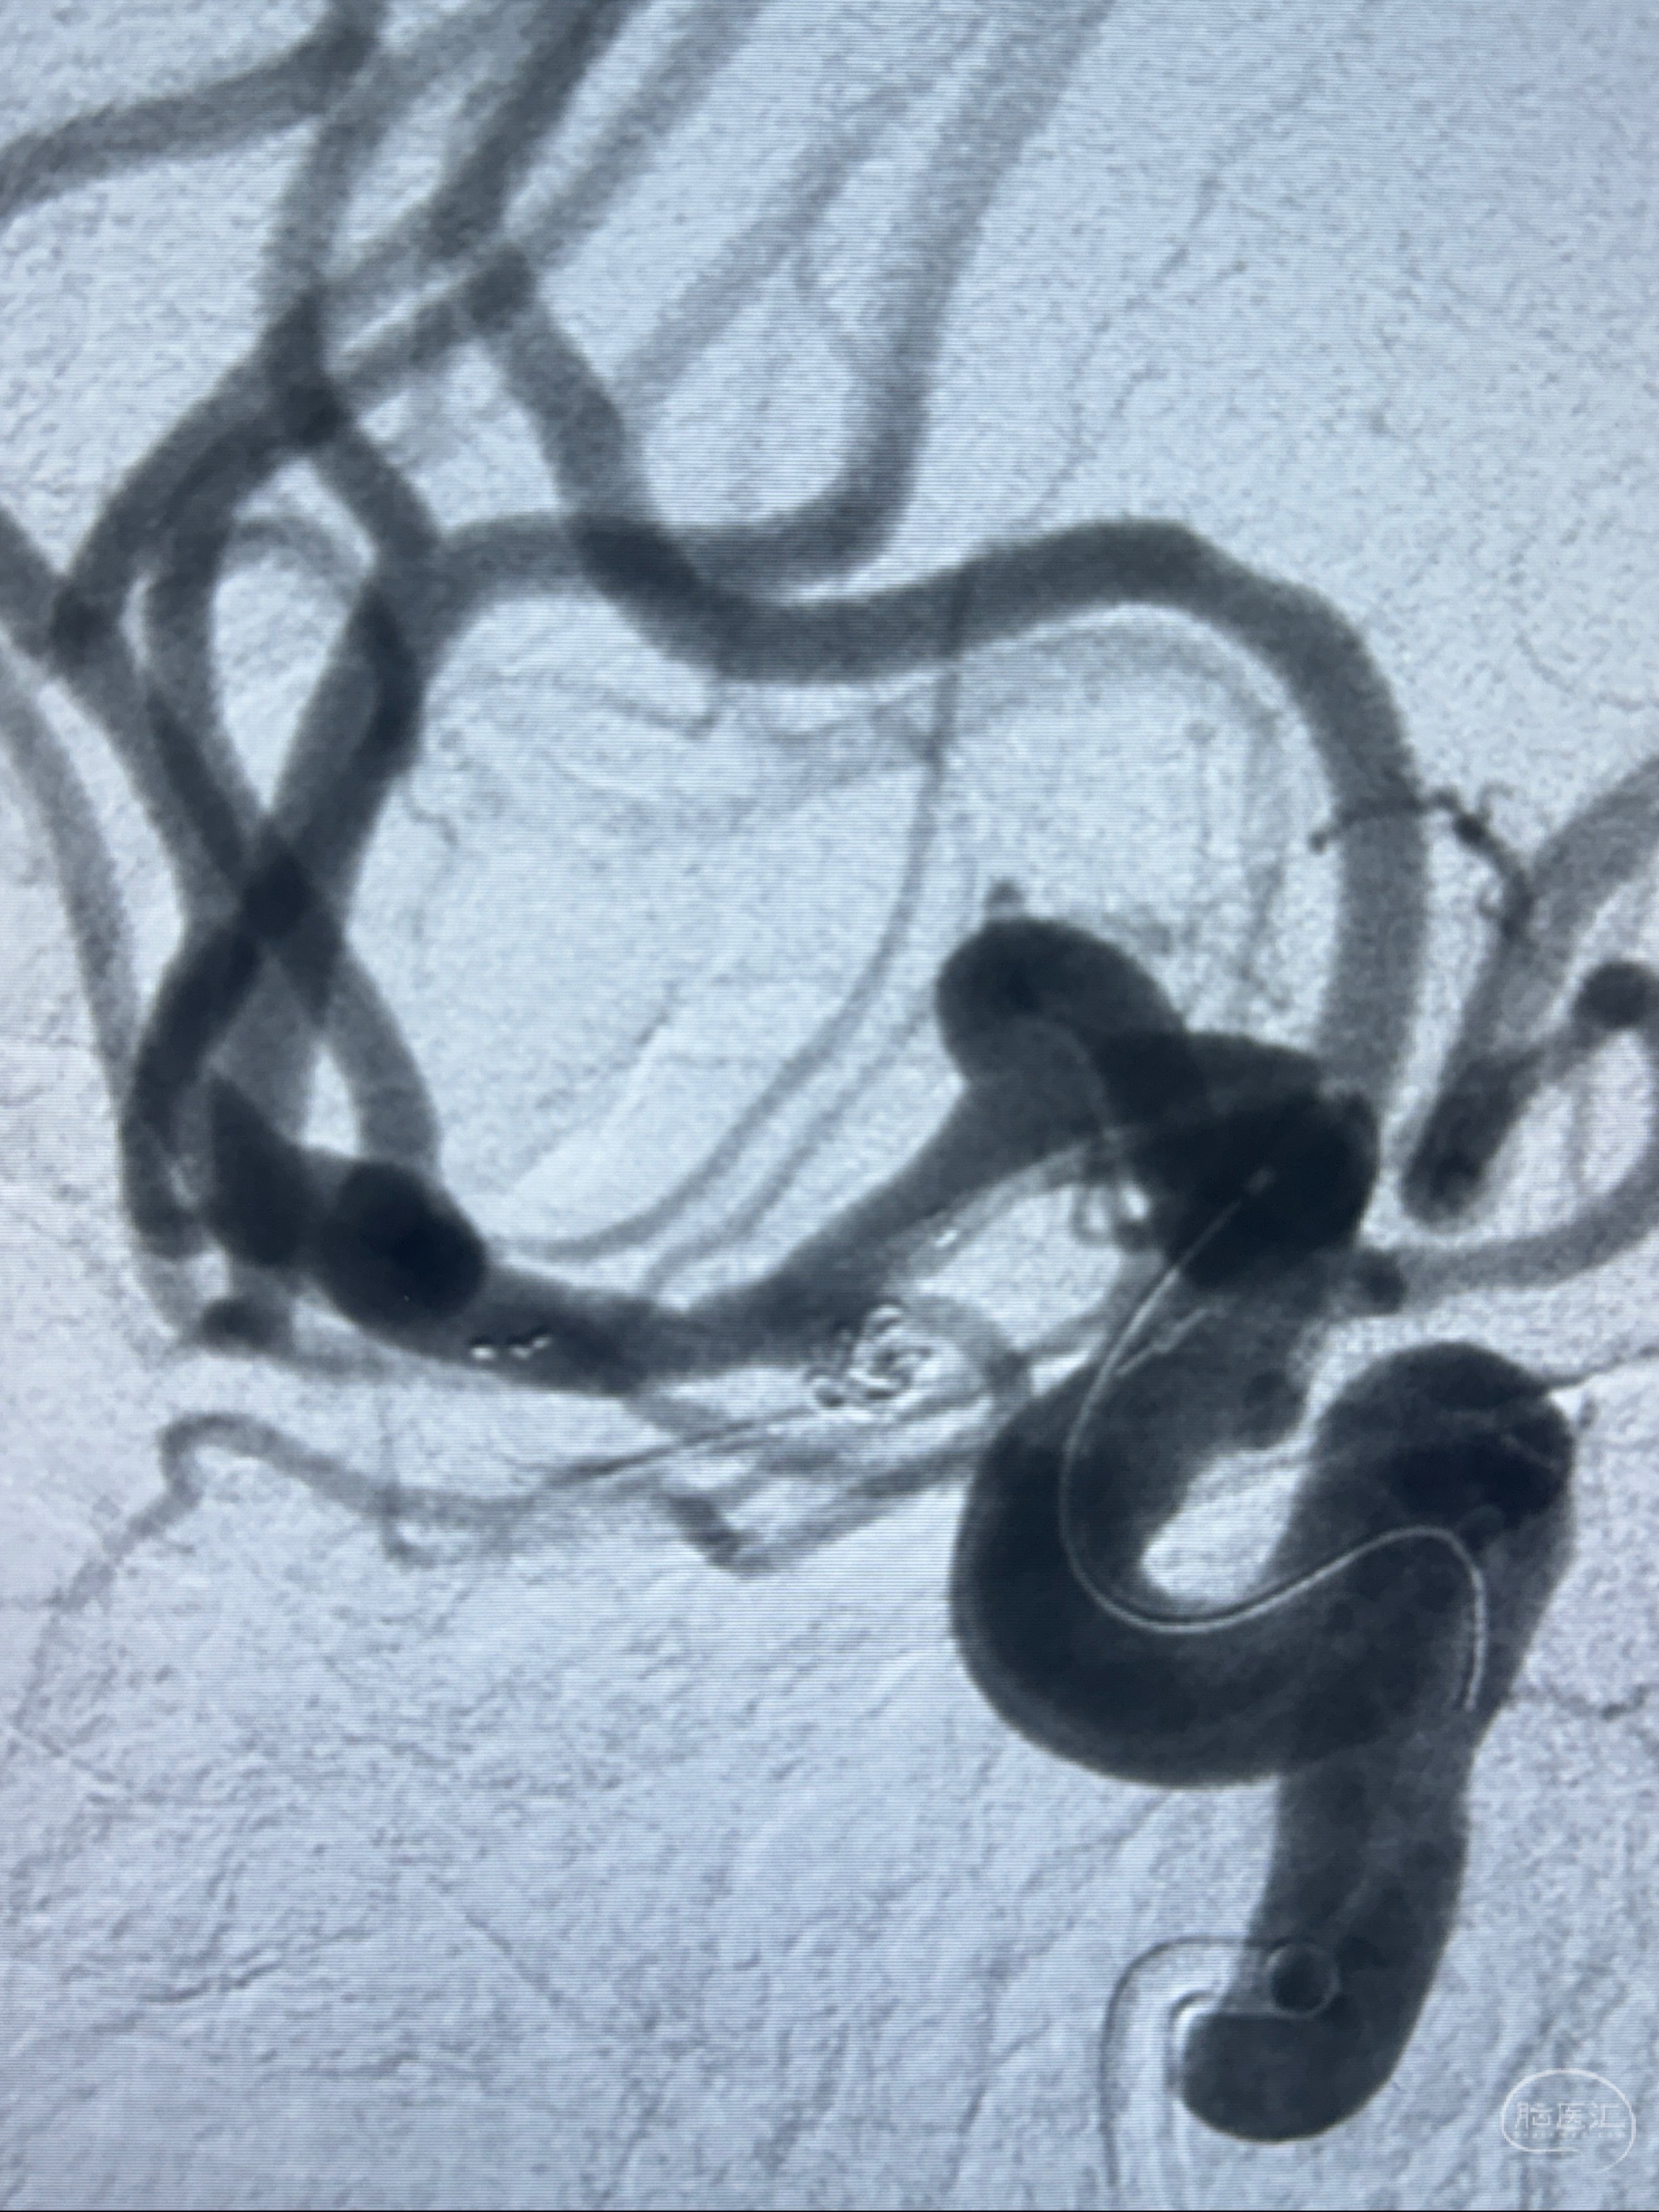

2023-11-24DSA:右侧大脑中动脉下干起始部动脉瘤,约2.3*2.5mm,形态规则

2023-12-04全麻下行支架辅助治疗

S-AB4-20mm

麻醉苏醒佳,遵嘱动作